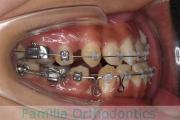

No.22V-398

- 叢生

- 14歳

- 男性

- 抜歯部位

- 上:

- 8448

- 下:

- 主な使用装置:

- FEA 022

- 治療にかかった費用:

- 88万円

八重歯が気になるのを治したいということで来院されました。上下左右から小臼歯を抜歯してマルチブラケット法にて治療を行いました。2年半、30回程度の通院が必要でした。叢生が強く、保定中の後戻りのリスクが高いため、保定がとても重要なケースです。